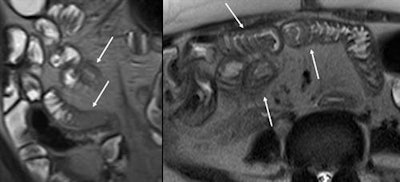

- Segmental stricture of the bowel on MRE with adjacent prominent collateral vessels detected in a patient with long-standing hypercoagulability state and findings of chronic mesenteric vein thrombosis should raise suspicion for ischemic strictures.